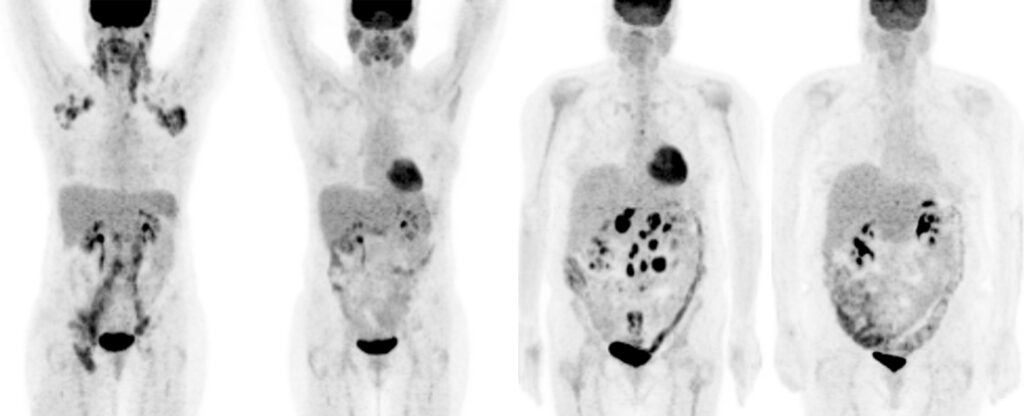

Si è conclusa con successo la prima fase della sperimentazione clinica di Cotara, un nuovo trattamento per il tumore al cervello in fase avanzata. La terapia, sviluppata dall’azienda americana Peregrine Pharmaceuticals, è basata sulla tecnologia denominata TNT (Tumor Necrosis Therapy), caratterizzata dall’impiego di un anticorpo monoclonale che veicola un isotopo radioattivo (Iodine 131) in grado di raggiungere e uccidere le cellule cancerose localizzate nel cuore del tumore, risparmiando i tessuti sani.

Dai primi risultati il prodotto è risultato ben tollerato, mostrando incoraggianti segnali di efficacia. E’ in corso l’arruolamento dei pazienti per due ulteriori trial, mirati a testare Cotara rispettivamente su pazienti affetti da glioblastoma multiforme recidivante e su pazienti alla prima ricaduta.